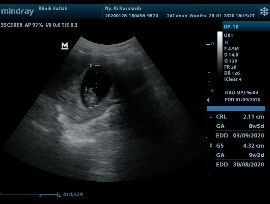

Assalamualaikum bunda-bunda... Maaf, saya mau bertanya. Melihat dari hasil USG foto dibawah. Usia kandungan saya yang benar adalah 8W5D atau 9W2D .. ? Tulisan sebelah kanan. Mohon bantuanya ya bund.. mau 4 bulanan tapi masih ragu. Hehe Terima kasih